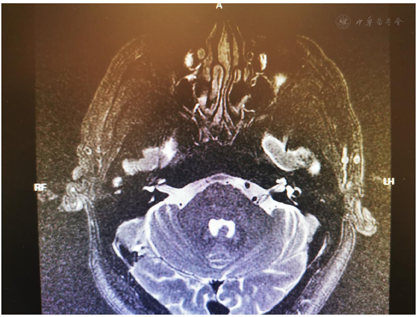

入院后完善相关检查:血常规、尿常规、血沉、凝血全套、前降钙素、梅毒系列+HCV+HIV 、乙肝三系+梅毒系列+HCV+HIV、大便常规+OB、生化分析、肿瘤相关物质测定、肿瘤系列均未见明显异常;术前头颅CT、颅脑MR检查排除了桥脑-小脑角占位病变,使用三维飞行时间磁共振血管造影(3D-TOF MRA)未见双侧面神经根遭受伴行血管压迫(图1)。术前面部表面肌电图可见双侧眼轮匝肌同步收缩和口轮匝肌爆发性放电,未见异常肌电反应(abnormal muscle response,AMR)。

患者双侧眼睑痉挛及口下颌肌肉不自主抽动,符合Meige氏综合征的临床诊断标准,结合头颅MRI检查(未见颅内占位病变及面神经根受血管压迫)和术前电生理检测,面部表面肌电图(sEMG)示双侧眼轮匝肌同步收缩和口轮匝肌暴发性放电,且无异常肌电反应(AMR),确诊为MS。